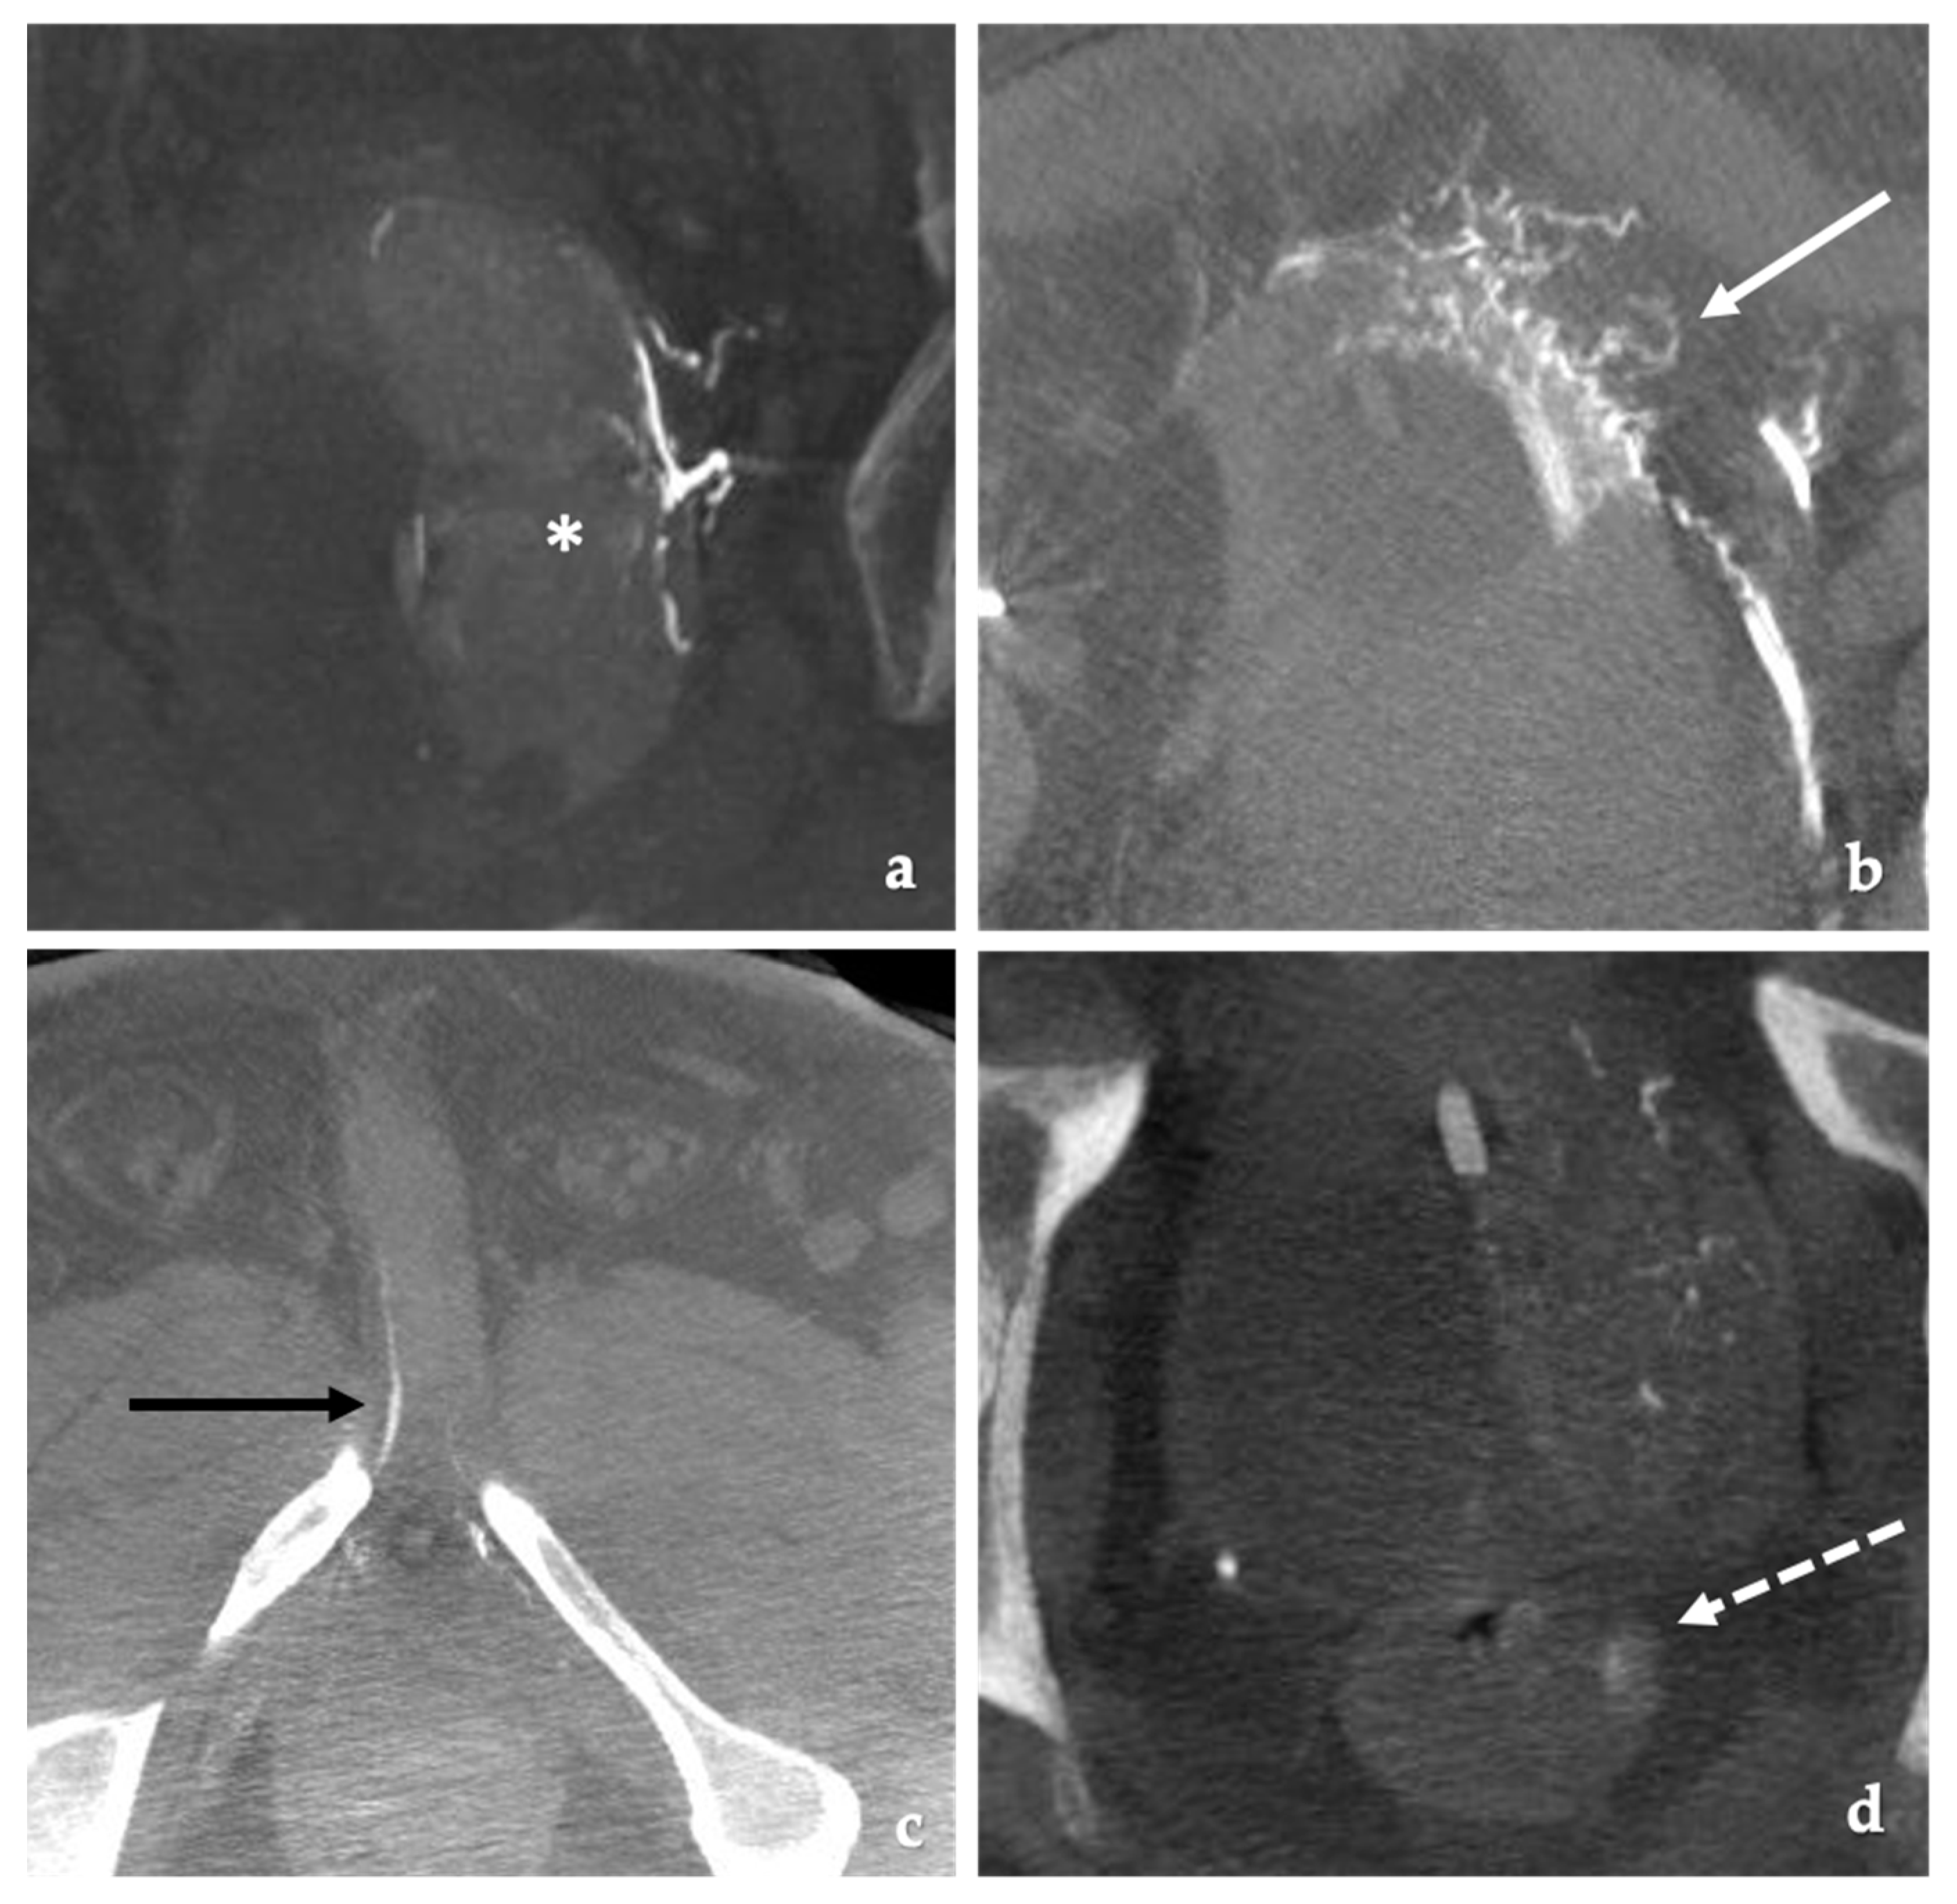

Many prefer the use of CT due to the speed of acquisition, spatial resolution and the ability to visualize very small arteries (Figure 1) [14,27,43]. CT angiography may also help identify the origins of the prostatic artery, which can be one of the more challenging steps in the procedure [27].

Figure 1.

Computed Tomography Angiography (CTA) is useful for PAE procedural planning. (a) CTA 3-D reconstruction using the dedicated prostate artery protocol demonstrates the prostate artery origin arising from the internal pudendal artery (white arrow). (b) Digital subtraction angiography (DSA) imaging performed at 35 degrees LAO projection shows the prostatic artery arising from the internal pudendal artery (black arrow) correlating with the CTA.

After identification, a 0.020” microcatheter is advanced into the prostate artery using a 0.014” wire. DSA imaging is then performed in the AP projection to identify and confirm filling of the prostate and evaluate for any sites of non-target embolization (Figure 2) [55]. Potential sites include the bladder, seminal vesicles, rectum and the penis. Cone beam CT or rotation angiography may be used to confirm no evidence of non-target embolization and to ensure the entire hemiprostate shows enhancement [26,27,43]. When using cone beam CT, the injection needs to be done very slowly to minimize reflux and contrast filling of more proximal branches thereby giving false positive sites of non-target embolization. Power injection at rates as low as 0.3 mL/s is performed [28]. Hand injection with the operator behind a floor mounted lead shield is another option.

Figure 2.

Examples of cone beam CT demonstrating target and non-target embolization. (a) Coronal reconstruction from a cone beam CT acquisition. Appropriate contrast enhancement of the left hemiprostate (white asterisks) with contrast injection of the left prostatic artery. (b) Axial cone beam CT image. Non-target filling of the bladder (white arrow). Foley catheter balloon in the bladder. (c) Axial cone beam CT image. Non-target filling of the penile artery (black arrow). (d) Axial cone beam image. Non-target enhancement of the rectum (dotted white arrow) with contrast enhancement of the prostate.